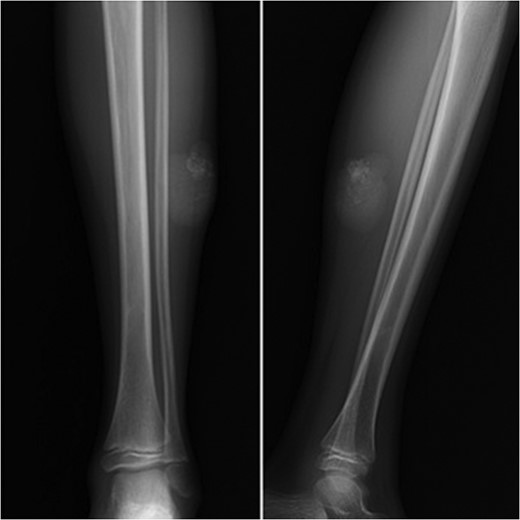

A 10-year-old boy presented with a 3-month history of pain and swelling in the left leg. Physical examination showed a 3 × 4 cm2 solid and mobile mass along the posterior aspect of the left leg. There were no history of trauma, weight loss or previous inflammatory disease. Radiographs showed calcification on the posterolateral side of the left cruris (Fig. 1). MRI indicated a solid soft tissue mass in the posterolateral side of the left cruris, which was observed to be hypointense in the T1A series, and hyperintense in the T2A series. The mass had regular margins, and exhibited peripheral contrast enhancement with a 41 × 30 × 27 mm3 size (Fig. 2). Lipoma, epidermoid cyst, sebaceous cyst, calcified hematoma and giant-cell tumor were considered in differential diagnosis. Incisional biopsy was performed. Histopathological examination confirmed as pilomatrixoma (Fig. 3). Thus, a complete resection of the mass was performed. There has been no recurrence, either clinically or radiologically, in subsequent 1-year period.

Image of calcification on the posterolateral part of the cruris.

During differential diagnosis, it is necessary to consider the possibility of dermoid cyst, sebaceous cyst, calcified lymphadenopathy, ossified or calcified hematoma, foreign bodies, giant-cell tumor and lipoma [7, 8, 10]. While pilomatrixoma does not exhibit a distinct and noticeable diagnostic feature during radiological examination, the presence of calcification is an important finding (Fig. 1). Although pilomatrixoma can be preoperatively diagnosed in 40% of cases with the aid of clinical and radiological methods, definite diagnosis requires histopathological examination [10].